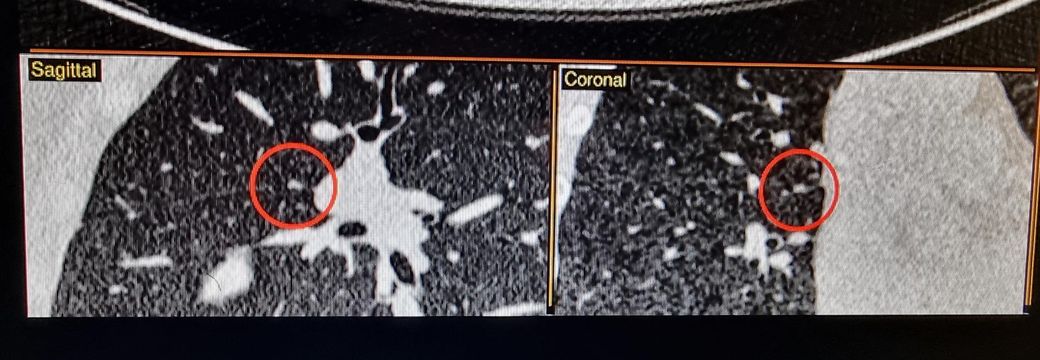

1슬라이드이선 하얀색 2슬라이드에선 음영진튼 회색 3슬라이드에선 아주연한 회색등..이면

순수가 아닌 고형있는 간유리일 확률이 있는건가요?

사진 봐주시길 부탁두려요

3thk 적혀있는거 제외하고 1thk입니다

밝고 선명한건 AI가 발견한것으로 두번째 사진이랑 같은거 같습니다.